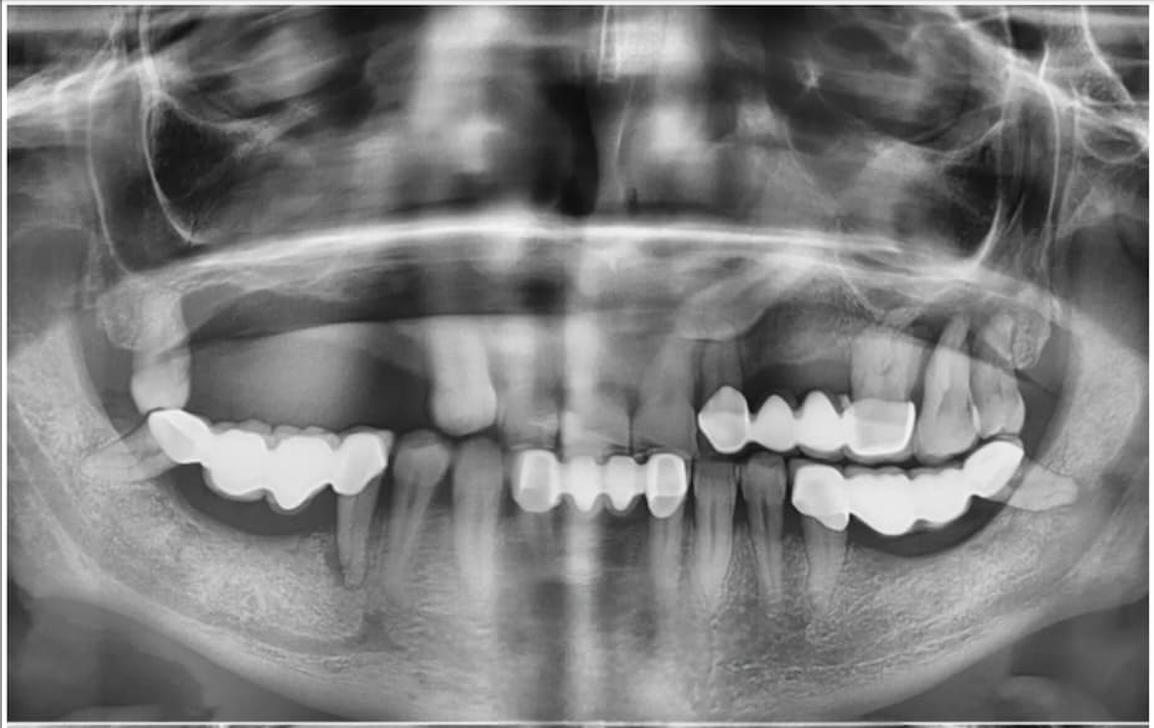

Patient Transformations

See the life-changing results of the ZAGA Philosophy.

Before

Before treatment

After

After treatment

Immediate Loading Success